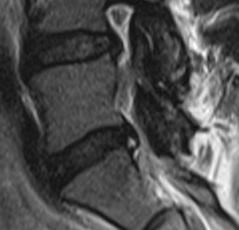

Discopathie MODIC 1 évoluant en MODIC 2. Notez le respect des corticales et l'absence de prise de contraste discale, malgré le franc hypersignal T2 du disque. Evolution à 1.5 ans en discopathie MODIC 2